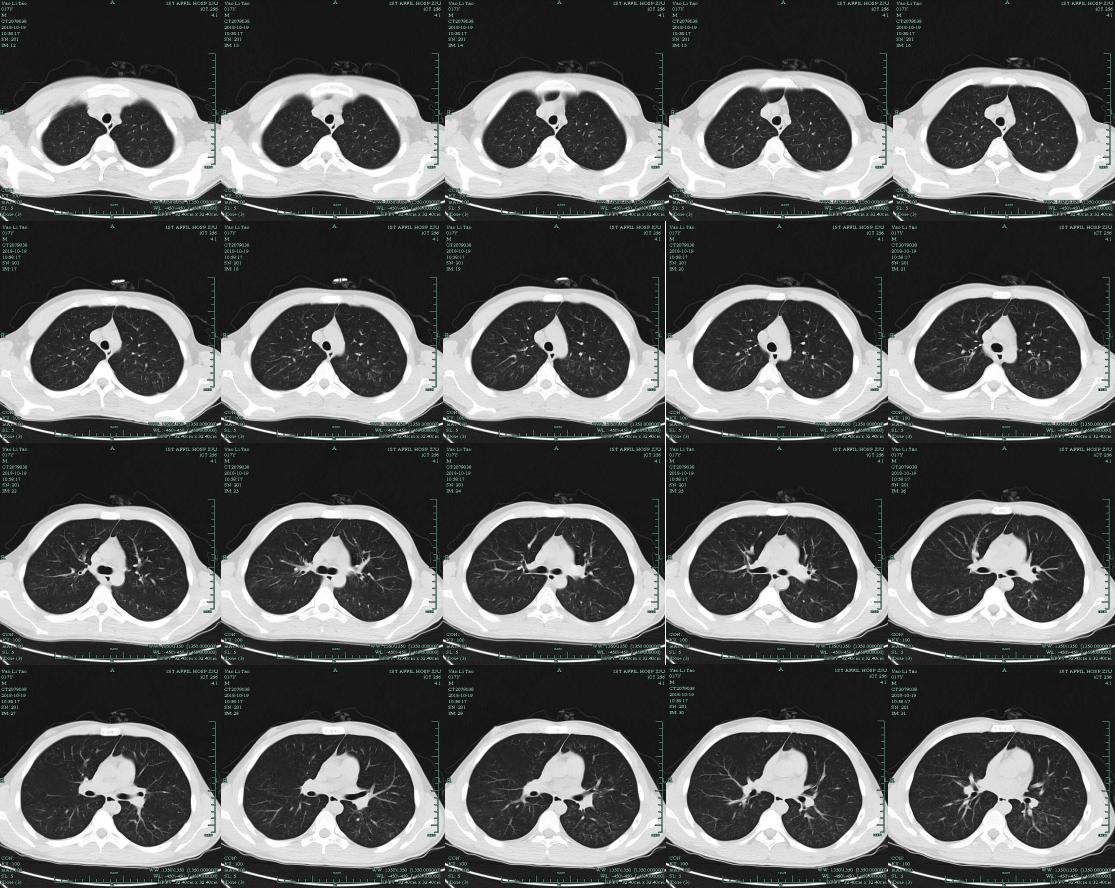

肺部CT(治疗后)提示双肺弥漫性病变,小叶性肺炎,左下肺斑片状阴影。

由于病人入院时病情严重,担心进行肺泡灌洗对他会有影响,所以进行了血mNGS检测……